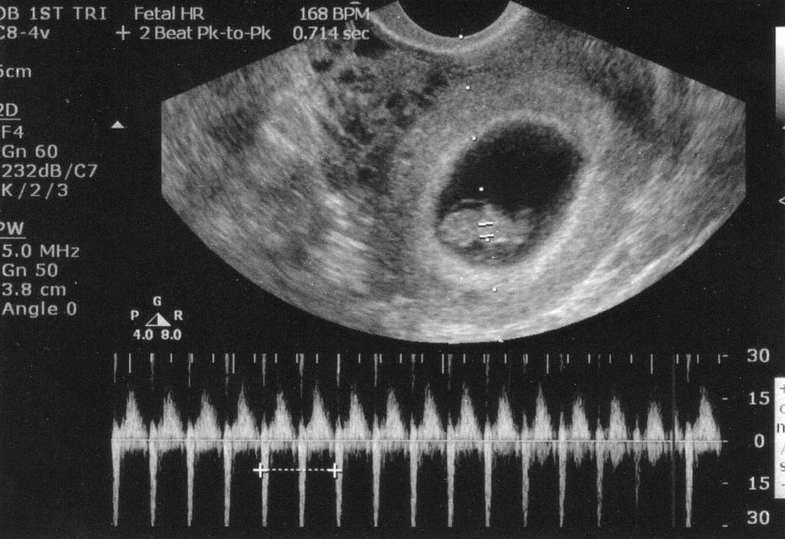

Mách mẹ cách nhận biết dấu hiệu thai 6 tuần khỏe mạnh 2

Tim thai bình thường là một trong những dấu hiệu thai 6 tuần khỏe mạnh

Nhịp tim

• Thai nhi 6 tuần đã có tim thai, nhịp tim mỗi phút từ 160 đến 180 lần, so với nhịp tim của mẹ thì nhanh hơn gấp đôi.

• Ở thời điểm này, thai nhi có điện tâm đồ cũng tương tự như người trưởng thành.

• Lúc này, cha mẹ thường muốn biết về giới tính của con. Nhiều người tin rằng đo nhịp tim thai 6 tuần có thể biết là con trai hay con gái. Nhưng thực tế, kết quả này không chính xác hoàn toàn.

• Theo nghiên cứu về giới tính và nhịp tim, không có sự khác biệt giữa nhịp tim của bé trai và bé gái. Ngoài ra, thai nhi lớn lên thì nhịp tim cũng thay đổi. Do đó, việc dự đoán giới tính thai nhi qua nhịp tim không mang lại kết quả chính xác.

• Ba mẹ cần đợi thêm một thời gian, lúc đó có thể nhìn thấy rõ thai nhi là con trai hay gái qua hình ảnh siêu âm.